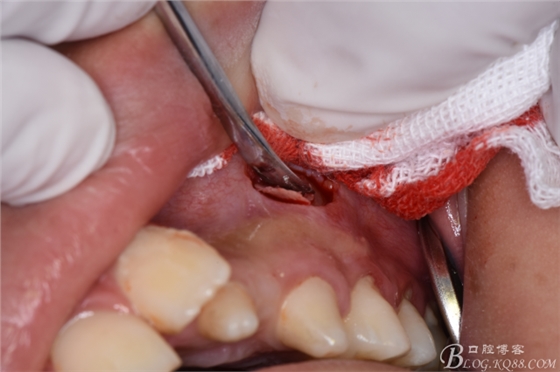

圖10.去骨

圖11.骨鑿去骨

圖12.暴露出23牙冠多唇面